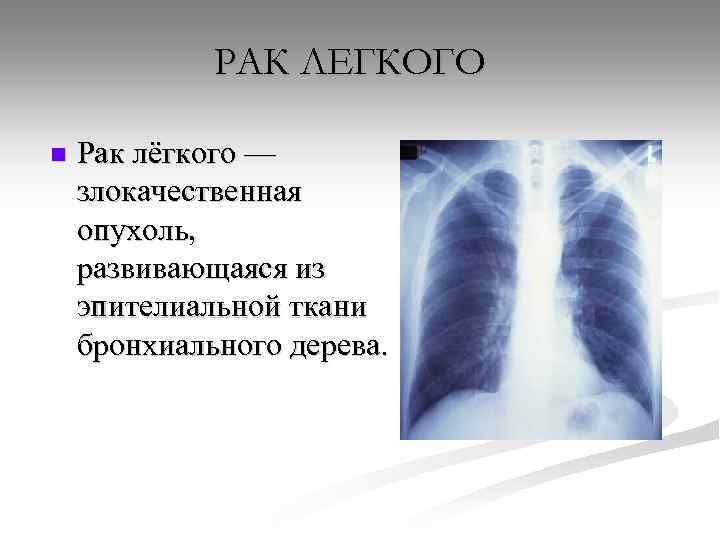

Несмотря на прогресс в медицине, рак продолжает убивать: в году от него погибло 9,6 миллиона человек. Из 18 миллионов ежегодно выявляемых случаев онкологических заболеваний около двух миллионов приходится на рак легкого. Все о нем — в материале Европейской клиники. Рак легкого или, как его еще называют, бронхогенный рак, — злокачественное новообразование легких, происходящее из эпителиальной ткани бронхов различного калибра. Оно может быть центральным, периферическим или массивным, то есть смешанным, в зависимости от места образования. Они отличаются не только способом роста и распространением, но и методом лечения.

Рак легких — это злокачественное образование, которое возникает в слизистых оболочках и железах бронхов и легких. Злокачественные клетки делятся достаточно стремительно, что позволяет опухоли быстро развиваться и расти. Если больной не получает необходимого лечения, то раковые клетки распространяются по всему организму, поражая при этом жизненно важные органы: сердце, мозг, кости, органы пищеварения, сосуды, лимфатическую систему. Расходясь по всему организму, раковые клетки образуют метастазы — вторичные образования злокачественной опухоли. Развитие раковой опухоли легких разделяют также на три стадии:. При образовании дифференцированной плоскоклеточной опухоли деление клеток достаточно медленное, недифференцированная наоборот развивается весьма стремительно, дает многочисленные метастазы. Наиболее опасным признан мелкоклеточный рак легкого, так как развитие его происходит стремительно и бессимптомно, очень рано появляются метастазы. Прогнозы у такого рака достаточно плохие.